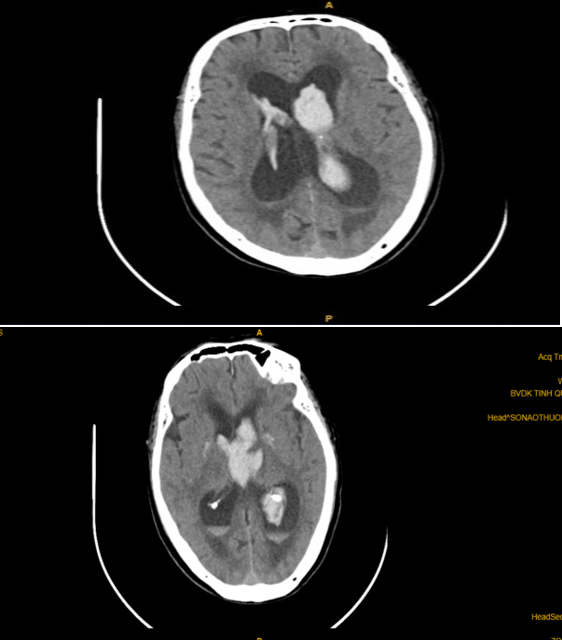

Bệnh nhân xuất huyết não thất được đặt EVD và bơm tiêu sợi huyết

CT sọ não trước đặt EVD